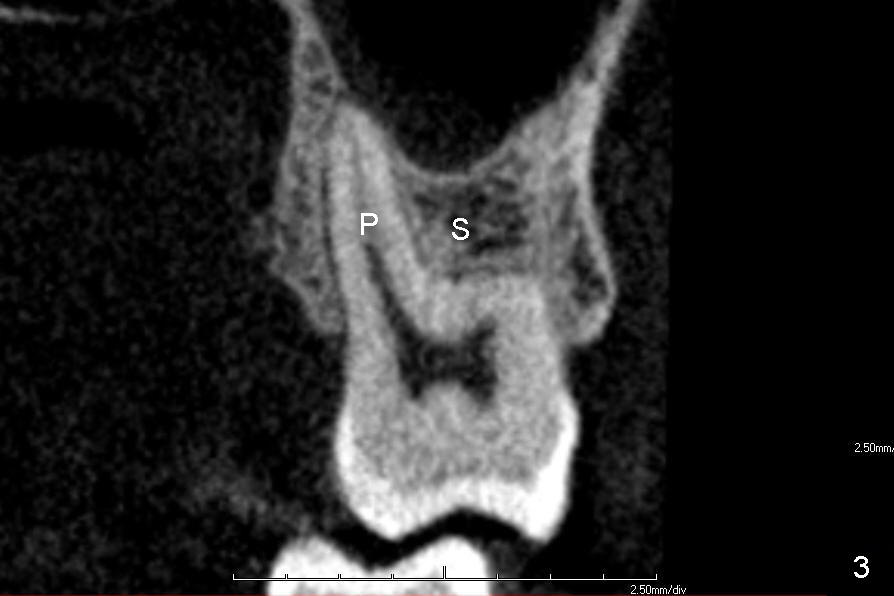

A 60-year-old man requests replacing the teeth #2 and 3, which have root fracture. Both of these two teeth have 3 roots (palatal (P), mesiobuccal (MB) and distobuccal (DB) (X-ray not shown). CT images from a different patient are used instead (Fig.1-3). The upper left image of Fig.1 (i.e., Fig.2) is an axial section, lower left (Fig.3) coronal and lower right sagittal.

If the septum is small or destroyed by the infection, an implant will be placed in the palatal root (Fig.5), since it is the biggest among these 3 roots (Fig.2). The advantage is that the implant is longer than that placed in the septum (Fig.8). The drawback is that the implant is off center (Fig.5, as compared to that placed in the septum (Fig.8)). The implant placed in the palatal socket is relatively small in diameter. The whole socket will not be occupied by the implant. Collagen membrane will be used to help close the socket as well as bone graft.